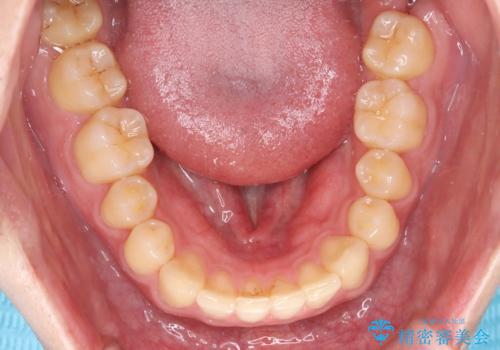

上顎中切歯間の隙間の他にもフロスが抵抗なく入るスペースが上顎は数か所ありました。スペースを閉じ下顎の歯列弓との調和をとるためIPRを行いました。

下顎の舌側傾斜気味の前歯も唇側へ歯軸傾斜させています。

矯正期間:1年2か月